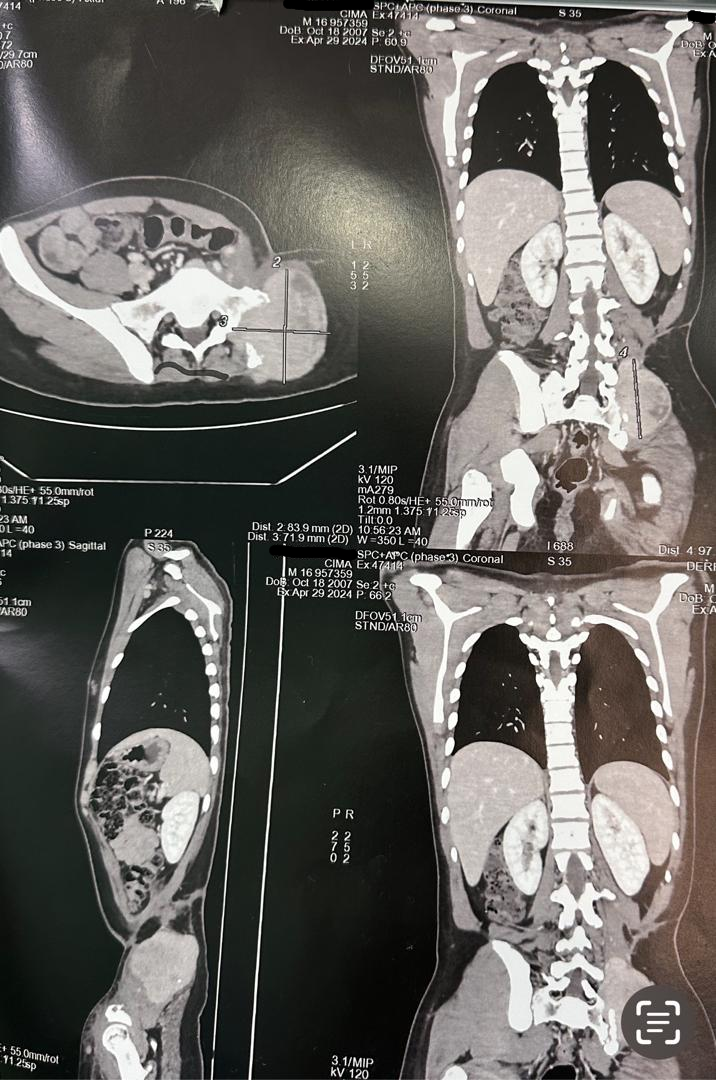

En Algérie, le cancer des os est relativement rare, représentant moins de 1 % de tous les cancers. Il existe des cas plus fréquents de métastases osseuses, lorsque des cancers provenant d'autres organes se propagent aux os.

Les cancers primaires des os (ceux qui débutent directement dans les os) sont peu fréquents, représentant moins de 1 % de tous les cancers. Chez les adultes, les cancers qui se propagent aux os depuis d'autres organes (appelés métastases osseuses) sont beaucoup plus courants que les cancers primaires des os.

Le traitement du cancer des os dépend de son origine. Les cancers osseux primitifs sont souvent traités par chirurgie, tandis que les métastases osseuses sont généralement traitées par radiothérapie en complément du traitement du cancer primaire.

- Chimiothérapie : Utilisée après la chirurgie pour traiter les cancers graves.

- Radiothérapie : Utilisée avant ou après la chirurgie pour traiter les tumeurs difficiles à atteindre.